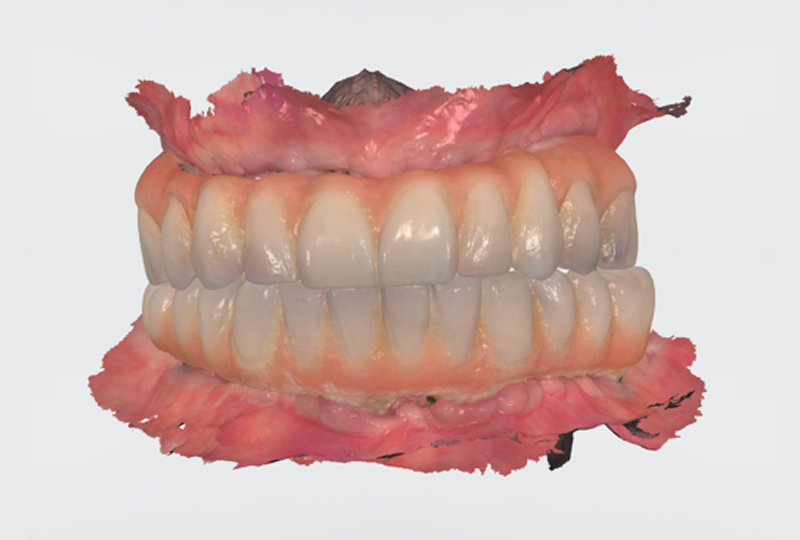

Le protesi definitive venivano prodotte in zirconia multilayer (ZOLID-GEN X 1100±150®, AMANN GIRRBACH) infiltrata e colorata con ceramiche fluide (MIYO®) sia nella parte bianca che in quella rosa. I T-base di connessione venivano incollati nel corpo protesico senza utilizzare nessun modello in gesso di riferimento. Nel terzo e ultimo appuntamento consegnavamo le protesi definitive (Figure 21,22,23).